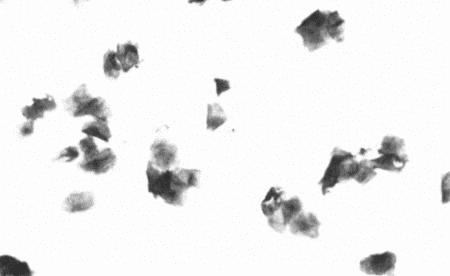

ВАГИНАЛЬНАЯ ЦИТОЛОГИЯ

Вагинальная цитология отражает гормональные изменения, происходящие в организме кошек (фиг. 2.2), особенно в период течки. Данный метод в племенном разведении кошек применяется реже, чем у собак, поскольку процедура может повлиять на ход цикла.

Во время фазы роста фолликулов в выделениях обнаруживаются поверхностные и кератинизированные клетки, наличие которых объясняется воздействием 17-β-эстрадиола. Процентное содержание безъядерных поверхностных клеток возрастает незначительно. В период фолликулярной фазы основной характеристикой вагинальных выделений является медленное сокращение количества клеток, содержащих ядро, промежуточных и базальных клеток. Однако указанные изменения у кошек менее выражены, чем у сук. Наиболее значимым индикатором активности эстрогена является осветление фона на предметном стекле, связанное с резким сокращением обломков разрушенных клеток и слизи. Содержание эозинофилов заметно ниже, чем у собак, эритроциты отсутствуют.

Для интерэструса характерно преимущественное содержание промежуточных клеток с небольшим включением базальных, парабазальных и кератинизированных клеток. В целом именно обломки клеток придают образцу характерный вид.

На стадии анэструса клеток немного, выделения содержат в основном слизь, базальные или парабазальные клетки с редким включением промежуточных клеток. В некоторых случаях присутствуют лейкоциты.

Вагинальная цитология применяется для установления или подтверждения фолликулярной фазы (проэструса или эструса). Обнаружение сперматозоидов вскоре после копуляции позволяет подтвердить факт вязки.

Фиг. 2.2.

Вагинальные выделения кошки (а). Выделения, типичные для фазы эструса. Большая часть клеток представляет собой безъядерные кератинизированные клетки или клетки с пикнотическим ядром. Присутствуют промежуточные клетки (b). Выделения, характерные для метэструса, — «течки», иногда наблюдаемой у кошек в конце эструса. Присутствуют поверхностные и промежуточные клетки, повышено содержание лейкоцитов. Этот короткий метэструс наблюдается в течение 24–48 часов (см. Приложение)